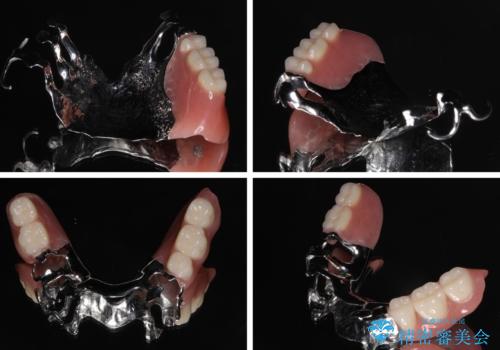

装着感の良い入れ歯を作りたい 金属床を使用した適合の良い部分床義歯

より適合の良い義歯とするため、セラミッククラウンなどは義歯の設計に合わせた土台の歯となるよう全て再製作をし、安定感に優れた義歯を製作することができました。